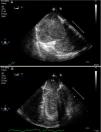

A 44-year-old man was admitted to our ICU due to thoracic trauma with associated bilateral pulmonary contusion. He developed severe refractory respiratory failure (PaO2/FiO2<100) and hemodynamic instability secondary to hypoxemia. Due to the inability to oxygenate the patient, it was decided to begin with veno-venous ECMO therapy. During cannulation of the femoral vein, a large thrombus (white arrow) was observed in the right atrium passing through the tricuspid valve into the pulmonary artery (Fig. 1); suddenly, the patient suffered cardiac arrest in pulseless electrical activity (Fig. 2), requiring advanced CPR maneuvers, recovering spontaneous circulation once ECMO therapy begun (Video). He remained under ECMO for seven days, after which, it was withdrawn due to respiratory improvement. He presented full neurological recovery.